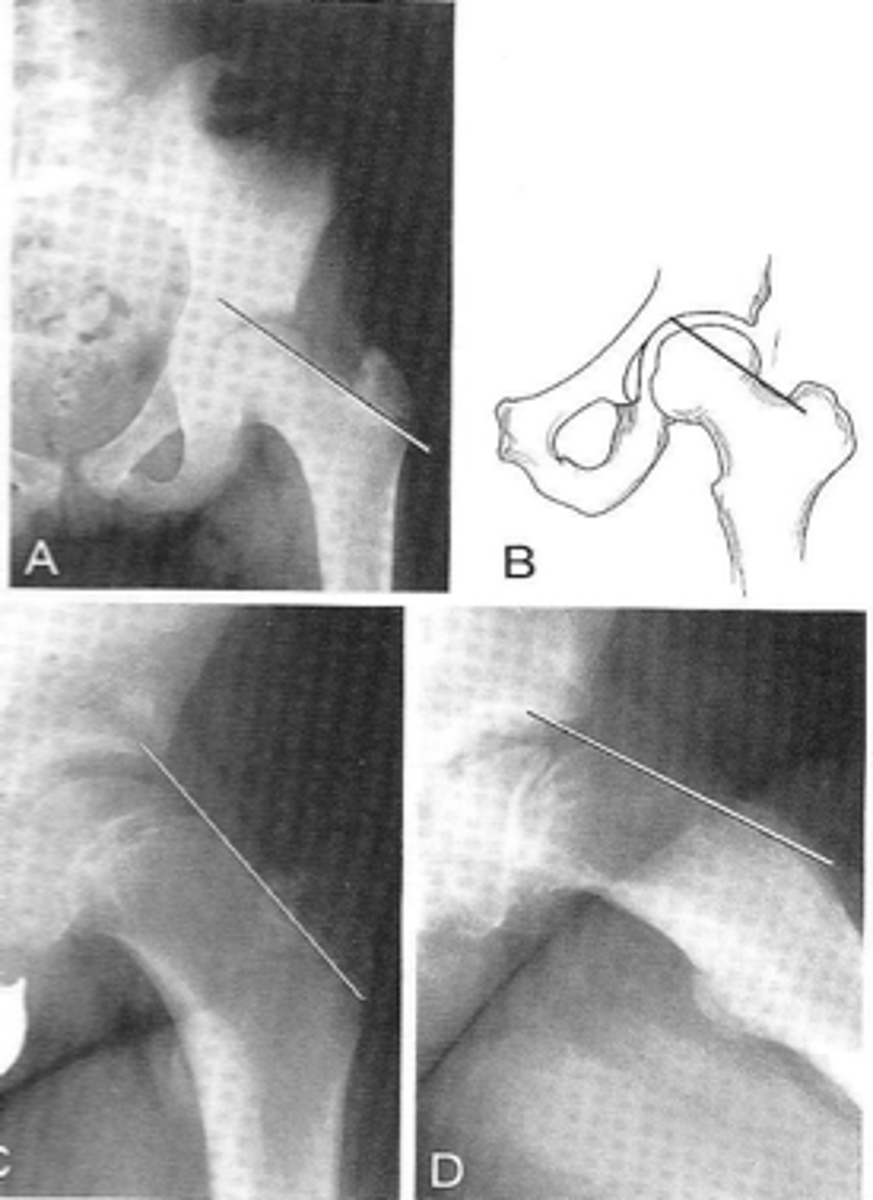

Shenton's line

ID measurement

<p>ID measurement</p>

New cards

- AP hip

- AP pelvis

What views are used to see Shenton's line?

- Smooth arc along femoral neck

- Obturator foramen

Shenton's line landmarks

Continuous and smooth

Shenton's line normal measurements

<p>Shenton's line normal measurements</p>

- Hip dislocation

- Femoral neck fracture

- Slipped epiphysis

Clinical significance of Shenton's line

<p>Clinical significance of Shenton's line</p>